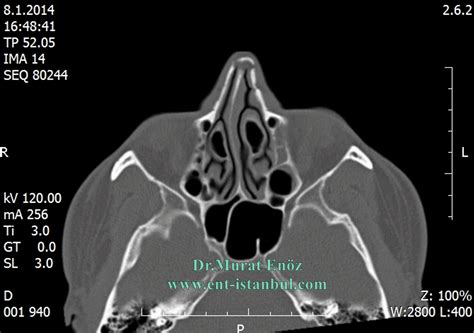

When an air cell develops within the middle turbinate, the structure expands significantly. This expansion is the defining characteristic of a Concha Bullosa. Depending on the size of the air pocket, the enlarged turbinate can press against the nasal septum or the lateral nasal wall, effectively narrowing the nasal passage and obstructing the narrow drainage pathways, known as the ostiomeatal complex, where the sinuses drain into the nose.

Diagnosing a Concha Bullosa typically requires more than a simple visual inspection during a physical exam. While an ENT might suspect the condition using an endoscope—a thin, flexible tube with a camera—a definitive diagnosis almost always relies on imaging. A Computed Tomography (CT) scan of the paranasal sinuses is the gold standard. It provides a detailed cross-sectional view of the nasal architecture, allowing the physician to measure the exact size of the air pocket and determine if it is contributing to sinus obstruction.

CT Scan Detailed imaging to confirm pneumatization and identify potential obstruction sites.